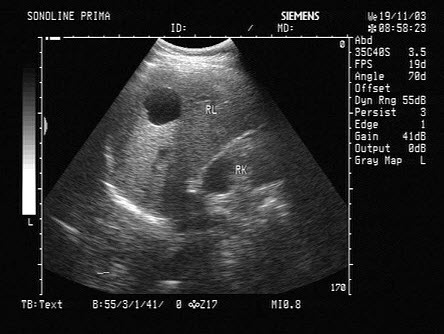

51、单项选择题

女性,25岁,停经35周。产前超声检查,图像显示的是胎儿的()

A.脊柱

B.肢体

C.颜面部

D.胸腔

E.胎头